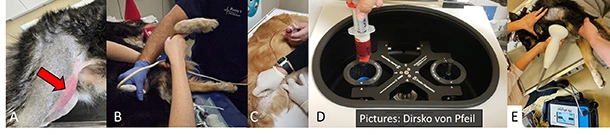

Muskelverletzung (A, roter Pfeil), Ultraschall (B), Eigenblutbehandlung (C, D), und Stosswellentherapie (E)